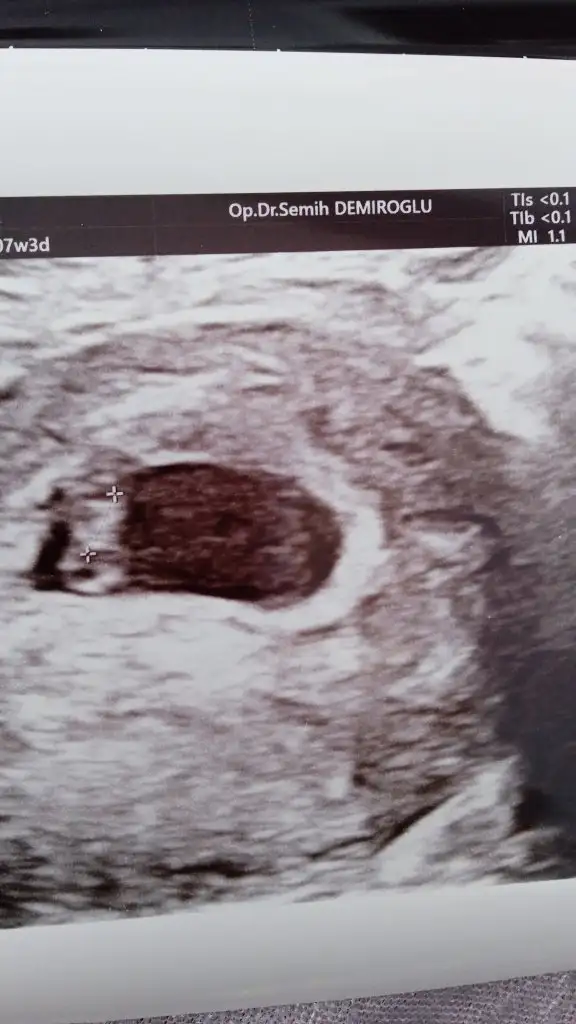

Keseye göre cinsiyet tahmininde neye bakılıyor 🤗 tahmin edebilen var mı acaba 🙃

Puxhu bir de benimkine bakar mısın 8 haftayız

Oğlumun kesesine benziyor..Erkek diyorum..Sağlıkla gelsin